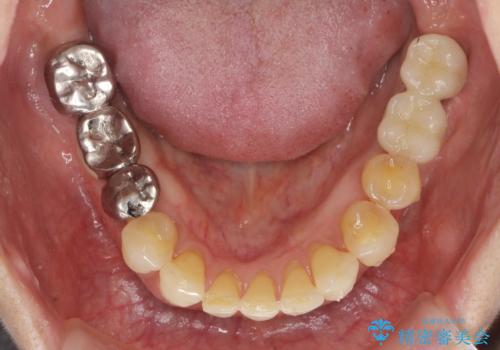

矯正治療を行うことで、歯を削ったり(ブリッジ)、手術の必要(インプラント)なく機能を欠損部位を無くし機能回復を達成することができました。